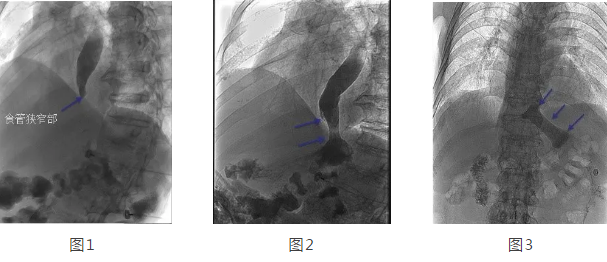

在韓國(guó)宏教授的帶領(lǐng)下,專家團(tuán)隊(duì)經(jīng)多方面評(píng)估后,決定在DSA下為劉大爺行食管造影 食管支架置入術(shù)。術(shù)中透視可見(jiàn)食管中上段擴(kuò)張明顯,食管下端賁門口明顯狹窄,造影劑淤積,呈線性緩慢進(jìn)入胃腔(見(jiàn)圖1),經(jīng)過(guò)準(zhǔn)確定位后,釋放食管支架,再次造影可見(jiàn)造影劑經(jīng)支架順利進(jìn)入胃腔(見(jiàn)圖2)。2天后再次造影見(jiàn)食管支架完全打開,位置正常,造影劑可順利通過(guò)支架(見(jiàn)圖3)。